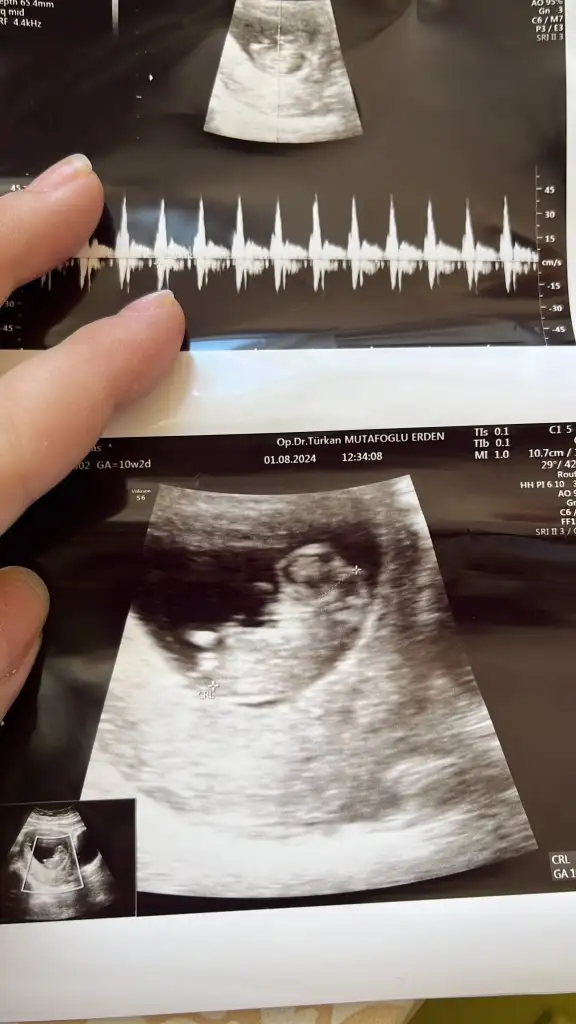

Bence erkek olacak neden bilmiyorum bende hamileyim öyle hissettim bide bana tahminde bulunur musunuz 13 haftalık olduBu da benimki teyzesi, sen bir tahminde bulunur musun

Erkek oldu kızBence erkek olacak neden bilmiyorum bende hamileyim öyle hissettim bide bana tahminde bulunur musunuz 13 haftalık oldu

Tahmin eder misiniz benimkinideErkek oldu kız

Maşallah lokumaTahmin eder misiniz benimkinide

Gerçekten mi insallah gönlümüzden geçen erkek nasip bakalımMaşallah lokumaiçimden erkek geçti çünkü aynı benim oğlumun ultrason görüntülerine bakıyor gibi hissettim. Çok benziyor, arkadan olan görüntüsü hele ki